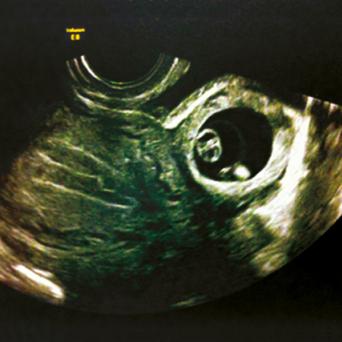

L’image

du jour

Illustration.